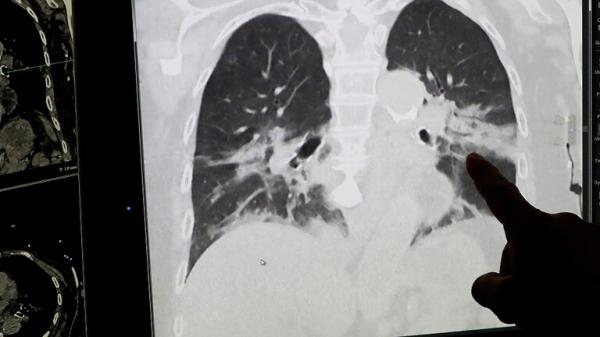

مع دخول تونس الموجة الثانية من الإصابات بفيروس كورونا، صمم فريق من المطورين برنامجا يستخدم تقنية الذكاء الاصطناعي لرصد أعراض مرض كوفيد-19 في الرئة.

ويعمل البرنامج عن طريق مقارنة الأشعة السينية لرئة مريض بأشعة المشتبه في إصابته بالمرض وتحدد الحلول الحسابية بعد ذلك ما إذا كان المشتبه في إصابته مصابا بالفعل بدقة تصل إلى 92%.

وتمت تغذية البرنامج بعشرات الآلاف من الصور الرئوية من مستشفيات في الصين وإيطاليا وإسبانيا لتعزيز قاعدة بياناته وتقوية قدرته على المقارنة.